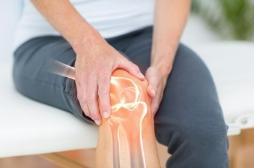

J ai Mal Bras et mains Bras et mains Tête et cou Torse et haut du dos Jambes et pied